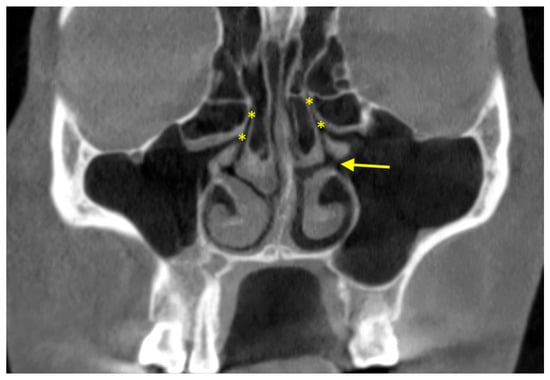

2.5. Septa